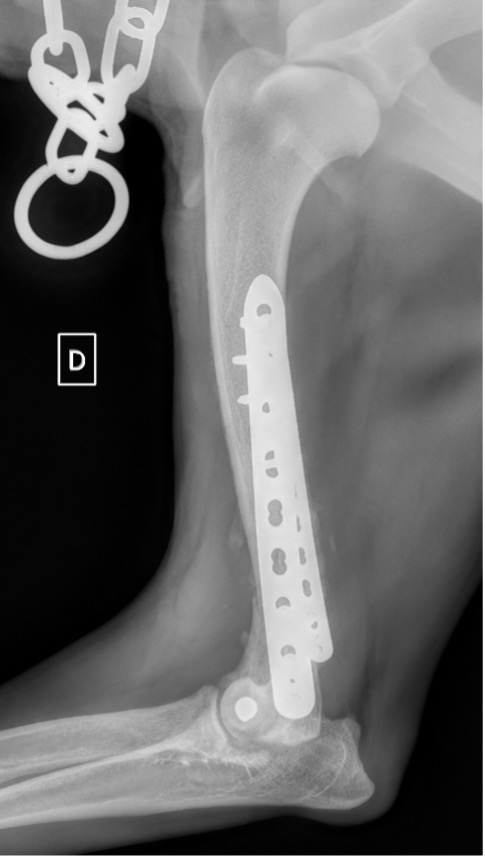

Exemple 2 :

Figure 4 : Pré-Op

Figure 5 : Post-Op Immédiat

Figure 6 : Post-Op 1 mois

Figure 7 : Post-Op 2 mois

Notre préférence va vers le placement de deux plaques humérales : une médiale de la plus grande taille possible et l’autre latérale, généralement d’une taille inférieure à la première. Dans l’exemple 1 (chat européen), une plaque de 2 mm est utilisée médialement et une plaque de 1,5 mm latéralement. Dans l’exemple 2 (chien Malinois), une plaque de 3,5 mm est utilisée médialement et une plaque de 2,7 mm latéralement.